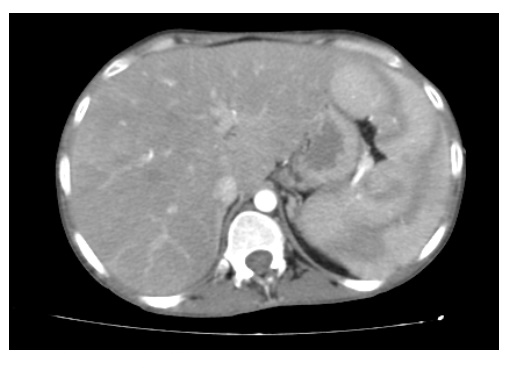

Hospital General Universitario Dr. ABSTRACT The study of smear of peripheral blood consists on specifying and informing the morphological alterations of blood elements; This is a simple, inexpensive, quick exam in reporting its results, but at the same time requires much care and experience, given the time exramedular interest that is devoted to its learning, the quality of the extension and its staining.

We present a literature review describing the variations of the peripheral lamina that can occur in diseases that most frequently affect the elderly, with the objective of offering a material for teaching residents of Hematology reitropoyesis Geriatrics. Estas anemias se presentan con frecuencia en el adulto mayor. Esta anemia se observa con frecuencia en el anciano por sangrado digestivo.